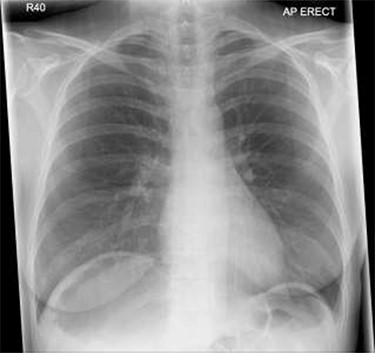

Patient initially diagnosed as biliary colic and surgical team had been contacted. Plain Abdominal radiograph showed dilated small bowels loops (Fig. 1). Chest radiograph revealed air under right hemi-diaphragm (Fig. 2). CT scan was done in emergency department and confirmed interposition of bowel between the diaphragm and the liver with a vascular/mesenteric pedicle swirl suggestive of malrotation or volvulus of the right colon. There was marked mural thickening and bold dilatation with high attenuation mucosa in keeping with closed loop obstruction and possible necrosis (Figs 3 and 4).

Chest X-ray shows air under diaphragm due to Chilaiditi syndrome.

Although an abdominal X-ray can be helpful in terms of diagnosis but not in all conditions, CT scan is an investigation of choice for such cases of caecal volvulus to make solid diagnosis and operate based on that evidence. In our patient the caecum, ileum and ascending colon were found entrapped and twisted at right hepato-diaphragmatic space resulting in an unusual Chilaiditi syndrome; hence a chest X-ray may give false impression of bowel perforation. Therefore, clinical correlation is always mandatory in order to consider different management options as in such cases.